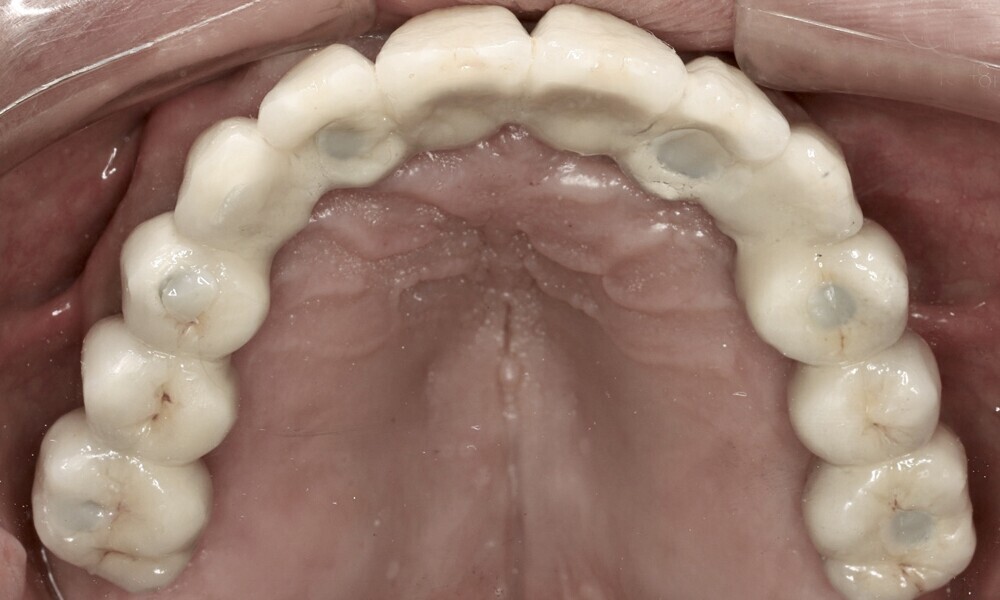

Employing a fully guided surgical protocol alongside a completely digital prosthetic workflow allowed for the precise design and milling of a PMMA provisional prosthesis (Figs. 34 & 35). The implant loading protocol implemented was immediate loading with equal distribution of forces across the entire prosthesis. The patient received the screw-retained provisional prosthesis on the same day. Temporary abutments (titanium copings) were placed on top of the screw-retained abutments. The spaces between the titanium copings and the provisional prosthesis were filled (Figs. 36–38). Any excess material was cut away, and the provisional prosthesis was subsequently polished to ensure a smooth finish (Fig. 39). The provisional prosthesis was then attached and securely fixed to the titanium copings to a 15 N cm torque (Fig. 40). Oral hygiene instructions were provided, and the occlusion was assessed (Figs. 41 & 42). A final control radiograph was obtained and confirmed that all parameters were within normal limits (Fig. 43).

During follow-up visits, the patient exhibited excellent healing and no postoperative complications (Fig. 44). The provisional prosthesis demonstrated optimal fit and stability, enhancing function and the patient’s comfort.

Four months later, we proceeded with the final prosthetic procedure based on clinical and radiographic evidence confirming osseointegration. The case was completed using Straumann RevEX scan bodies for a full monolithic design with a completely digital workflow. First, an intra-oral scan of the opposite arch was taken, followed by an intra-oral scan with the screwed-in temporary abutments. An intra-oral bite scan and an intra-oral scan of the soft tissue with the screw-retained abutments in place were then taken. The reverse scan bodies were attached to the provisional prosthesis, which was scanned extra-orally. Next, the prototype and verification jig were designed, followed by the milling of the prototype and verification jig (Figs. 45 & 46).